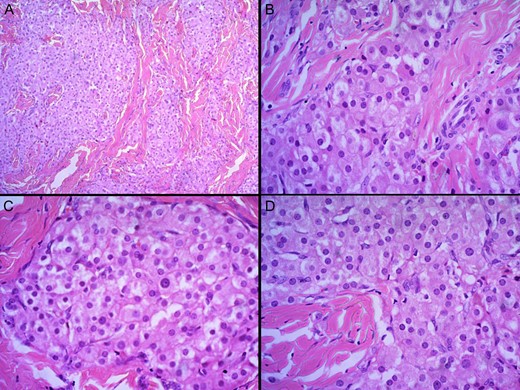

A biopsy of the right epididymis was performed. The sections revealed nodules of cells with intervening dense fibrous septae. The nodules comprised nests and cords of polygonal Leydig cells with abundant eosinophilic cytoplasm, uniform round nuclei and small nucleoli. Cell borders were distinct and a lymphoid infiltrate was present in the stroma (Fig. 1). Testicular tissue comprised of seminiferous tubules with thickened basement membranes. Residual testicular tissue showed predominantly germ cell aplasia with occasional tubules containing spermatogonia. Most seminiferous tubules contained only Sertoli cells. Spermatocytes, spermatids and spermatozoa were absent. Collections of Leydig cells were noted between the seminiferous tubules. Intratubular germ cell neoplasia or malignancy was absent (Fig. 2).

H and E staining viewed under ×4 (A) and ×40 (B–D) showing nodules of cells with intervening dense fibrous septae. The nodules comprised nests and cords of polygonal Leydig cells with abundant eosinophilic cytoplasm, uniform round nuclei and small nucleoli. Cell borders were distinct and a lymphoid infiltrate was present in the stroma.